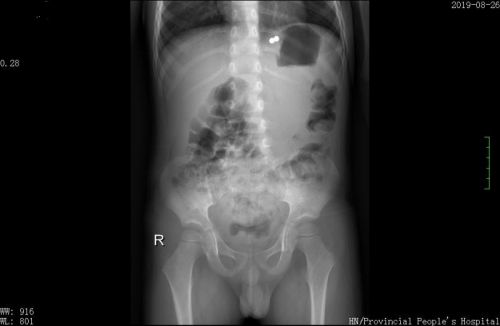

紧急透视检查发现失踪的2颗磁力珠在胃贲门处。

赶紧再进行胃镜检查,然而,在胃腔、食管内并未发现残余的珠子。又做了X光检查,这才发现2颗漏网之珠紧密吸附在胃与贲门的位置。再次胃镜发现,在食管靠近贲门和胃底靠近贲门处各有一个洞,2颗磁珠应该是相互吸引嵌入粘膜下组织“藏”了起来,所以未被发现。